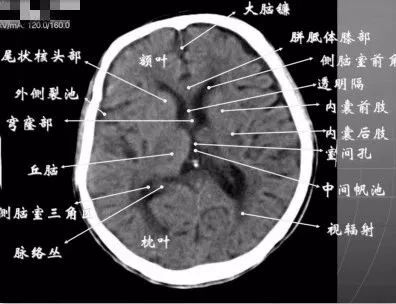

4、第三脑室上部层面基底核、丘脑。

内囊前脚(前肢);尾状核和豆状核之间。

内囊膝部和后脚(后肢):位于豆状核(由外侧的壳核和内侧的苍白球组成)及丘脑之间。

壳核的外侧:外囊、屏状核、最外囊、岛叶(脑岛)。

四叠体池:两侧枕叶之间,池内有松果体,向前与第三脑室连接。

基底节(基底核):埋藏在两侧大脑半球深部的灰质核团,是组成锥体外系的主要结构。

基底节区:概念不清。可能包括:基底节、黑质、红核、及其周围白质区域。

内囊:位于丘脑、尾状核、豆状核之间的白质区,是由上、下行的传导束密集而成。分为三部分:前肢、膝部、后肢。膝部有皮质脑干束;后肢有皮质脊髓束、丘脑皮质束、听辐射和视辐射。

外囊:是位于屏状核和豆状核之间的白质带,主要由岛叶发出的皮质被盖纤维组成。